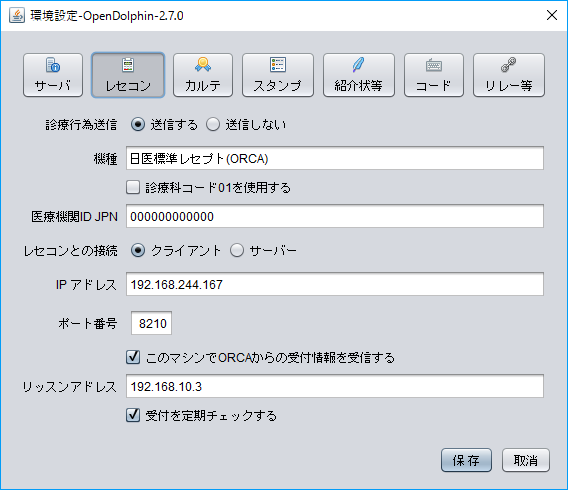

以前ブログで、OpenDolphin(電子カルテ)とORCA(日医レセコン)の環境構築について書いたところ、OpenDolphinデータベースを二次利用できるのかコメントをいただきました。

実際OpenDolphinで電子カルテを運用されている方の参考にもなるかもしれないので、仮想マシンでの環境構築とRstudioでの接続までを書いておきます。

インストール用のスクリプトは上記ブログ内のものとほぼ同じですが、OpenDolphinのDockerコンテナで使用しているPostgreSQLと、ORCAのPostgreSQLのポートがぶつからないように、Docker runするときにPort(5433)を指定しています(通常は5432)。RstudioもクライアントPCにインストールするのが面倒なので、Dockerコンテナで入れちゃいます。

では今回のポイントのOpenDolphinとRstudioの接続です。

OpenDolphinとORCAの簡単な環境構築

OpenDolphinは日医レセコンORCAに接続できる、オープンソースの電子カルテです。

極力インストールの手間を省略するためと、ホストOSの環境をよごさないために、VMwareの仮想マシンにUbuntu64,14.04LTSをインストールし、そこにORCAをインストールします。またOpenDolphinはUbuntuのDockerを利用してインストールします。

Ubuntuが苦手、Dockerがわからなくても環境構築できるように、シェルスクリプトを使ってコード入力を少なくすることにします。